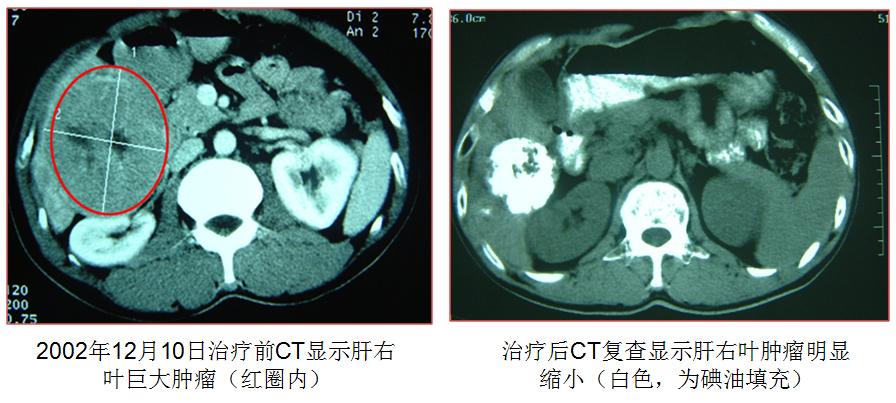

谭生来自广州以北150多公里的英德,男性,50几岁。2002年12月,他从广州市内一家医院转来我院,挺着的大肚皮与瘦削的面孔和四肢,形成鲜明对照。面孔暗黑无光,皮下隐约见扩张毛细血管,一副典型肝硬化面容。再查腹部,季肋下3厘米处可触及质地坚硬的肝边缘,腹部明显“移动性浊音”,提示中等量腹水。腹部CT上显示肝右叶有8-11 厘米大小的“占位性病变”,甲胎蛋白500 多。乙型肝炎病毒感染“小三阳”,转氨酶150单位,胆红素轻度升高,白蛋白31克,稍降低。肝活检:肝细胞性肝癌。诊断:肝癌,伴慢性乙型肝炎、肝硬化。先给予利水护肝治疗,再做肝动脉碘油化学栓塞(TACE),最后经皮冷冻消融。治疗后每天发热,上午10点开始,39.5°C左右,2-3 小时后自退。持续3个月左右,肝内肿瘤明显缩小,甲胎蛋白降到正常。此后每年均来医院复查,未见复发,直到一年前,肝右叶新生3-4 块,接受TACE和经皮冷冻,一度控制,但近1个月,在肝左右叶再出现多发性新的病变,甲胎蛋白明显上升。